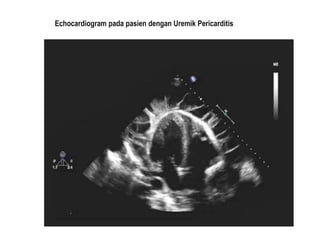

Echocardiogram pada pasien dengan Uremik Pericarditis

Echocardiogram pada pasiendengan Uremik Pericarditis